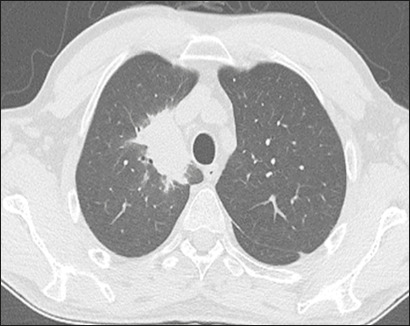

Results: Forty-nine patients (30 males; mean age, 61 years) were included. We identified Gram-negative bacteria in 45 patients, Gram-positive bacteria in 13, and fungi in three. Pulmonary abnormalities were bilateral in 73% of the patients in the sample, and there was no difference in prevalence between the upper and lower lung fields in 53%. Common alterations were consolidation, in 73% of the patients, bronchial wall thickening, in 71%, bronchiectasis, in 55%, and nodules, in 53%; extrapulmonary findings were less common, being identified in ≤ 27%. Pulmonary findings were typically bilateral and without a predominance between the upper and lower lung fields (p < 0.05). Common associations were between consolidation and bronchiectasis, between nodules and bronchial wall thickening, and between bronchiectasis and bronchial wall thickening (p < 0.05 for all).

Conclusion: The CT manifestations of pneumonia in patients with hematologic diseases not responding to empirical therapy can resemble those of lobular pneumonia with airway inflammation. For that reason, as well as because multiple pathogens can be present in the same patient, examination of bronchoalveolar lavage fluid can be necessary.